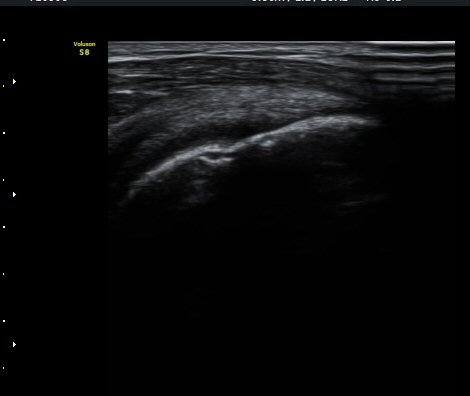

¼ö¾×Àú·ù°¡ °üÂûµÈ´Ù(±×¸² 1, 2). °ß°©ÇÏ±Ù°Ç Á¾´Ü¸é°Ë»ç¿¡¼­ °ß°©ÇϱٰÇÀÇ °üÀý³»ºÎÀ§(±×¸² 3)

¿Í ¼Ò°áÀý »óºÎ(±×¸² 4)¿¡¼­ ƯÀÌ ¼Ò°ßÀ» º¸ÀÌÁö ¾Ê´Â´Ù.